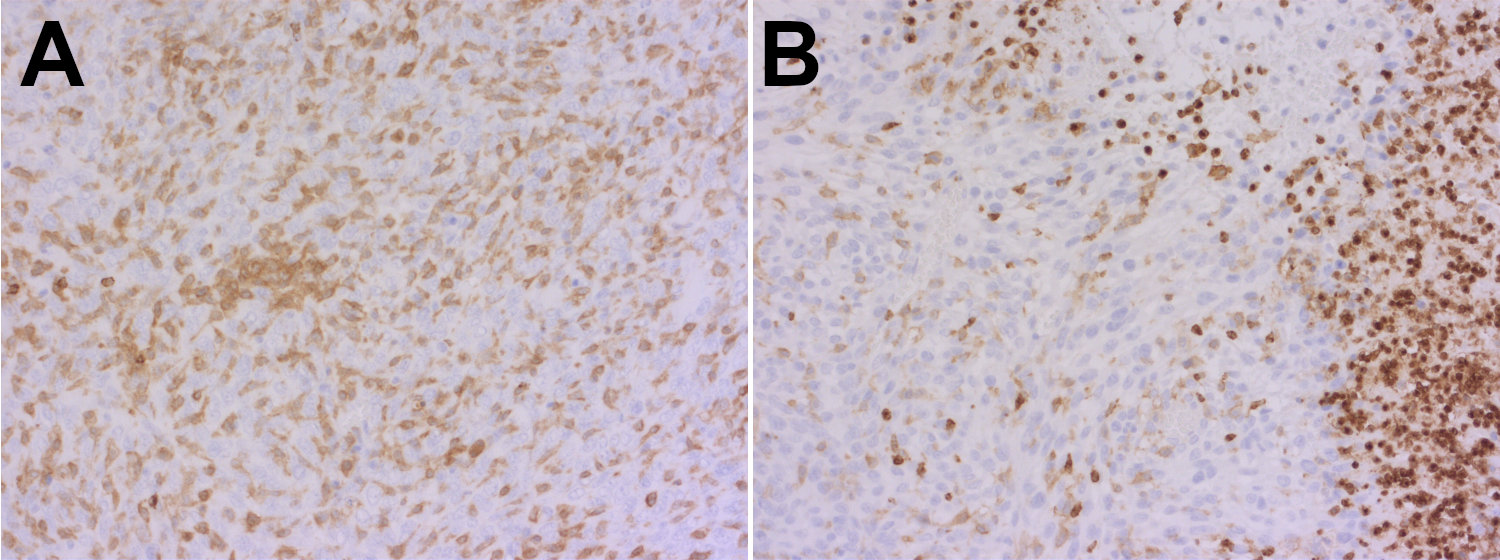

Synaptic Systems - alpha/beta Synuclein。HistoSure - CD11b。M4 Exhaust GSX-R1000 2001-2002 ボルトオン カーボン SU9534。ヨリ キティリボンレイヤードブラウス 36ヨリ リボンチュールジレ 38おまとめ割適応しております。【レア】patagonia Girl’s Baggies Shorts 限定商品。選べませんので、ご了承くださいませ。ローレンラルフローレン サマーニットM Ralph Lauren 訳あり。。HistoSure - CD11b。※※トラブル防止の為、プロフィール、商品の説明を必ずご確認した上でご購入をお願い申し上げます。※※生産工場からの直接仕入を行っておりますが、サンプル品や工事余剰品の為、タグ類は一部タグ付きランダムに発送いたします。トゥモローランド ノースリーブニットソー。値下げ☆L'Appartement ニット ブラック。ディテールやサイズに差異が生じる場合もあります◯インポート品のため、こだわりのある方は店舗より定価で購入してください。◯発送は2-3週間前後になります。新品未使用 シェリエ sheller シンプルリブニット